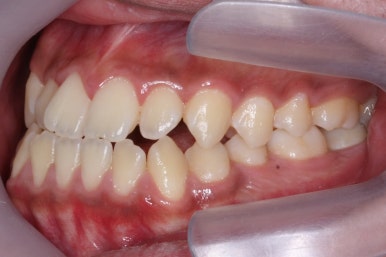

위 사진들은 부산주걱턱교정 키다리아저씨치과에 내원하셨을 당시의 입안 모습입니다.

입 안의 모습에서도 주걱턱의 특징으로는

하악이 앞으로 나와있습니다.

윗니는 뻐드러지고 아래 앞니는 뒤쪽으로 쓰러져 있습니다.

교합이 맞지 않습니다.